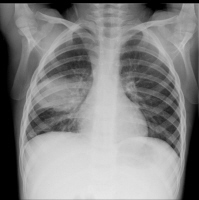

پنومونی

پنومونی عفونت دستگاه تنفسی تحتانی است که مجاری وبافت ریه را در گیر خود کرده وباعث اشغال فضای آلوئولی (کیسه های هوایی) می شود. اگر چه شایعترین علت پنومونی بیماریهای ویروسی است ولی در این بخش منظور ما از پنومونی، پنومونیهای چرکی است که می تواند خود را به صورت تب،افزایش تعداد نفسها وتنفس مشکل نشان دهد.

پنومونی ممکن است باعث ایجاد مایع داخل جنبی گردد (جنب به فضای بین ریه و قفسه سینه گفته می شود) در این مواقع مایع در فضای بین ریه وقفسه سینه ودر داخل جنب دیده می شود. عفونت والتهاب می تواند باعث  تخریب بافت ریه و گشاد شدن مجاری تنفسی گردد که این خود زمینه را برای عفونتهای بعدی آماده می کند. از موارد دیگر آبسه ریه می باشد که معمولا بدنبال آسپراسیون در کودکان ایجاد می شود.ارزیابی پاسخ به درمان انتی بیوتیک در پنومونی بیشتر بر اساس یافته های بالینی مانند کاهش تب و دیستریس  تنفسی و بهبود حال عمومی بیمار می باشد ولی یافته های غیرطبیعی در عکس سینه ممکن است برای چندین هفته باقی بماند.